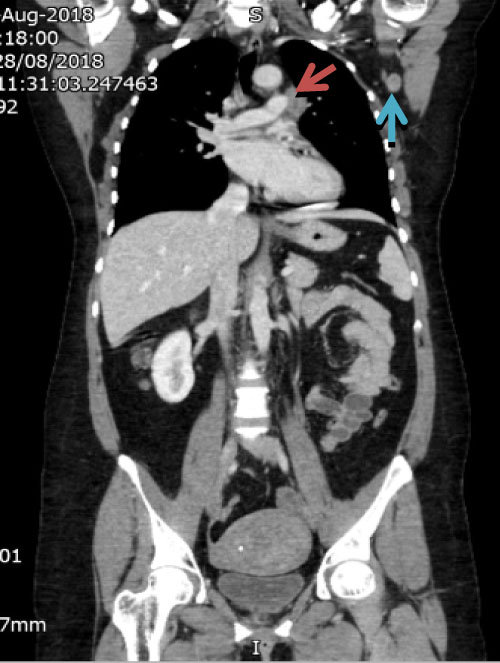

As per our unit protocol, she underwent contrast enhanced magnetic resonance imaging (CE-MRI) of brain inclusive of stereotactic planning sequence (Figure 2), CT chest, abdomen and pelvis (Figure 3).

Figure 3: Shows left hilar lymph node abutting left pulmonary artery (brown arrow) and in the left axilla (blue arrow). View Figure 3

MRI was reported as multicentric lesion likely primary glioma and metastatic deposits as possible differentials, but unlikely to be an abscess due to lack of diffusion restriction in the centre of the lesions. CT chest, abdomen and pelvis (CAP) found incidental left hilar and axillary adenopathy for which guided biopsy was advised but was not followed up on at this point.